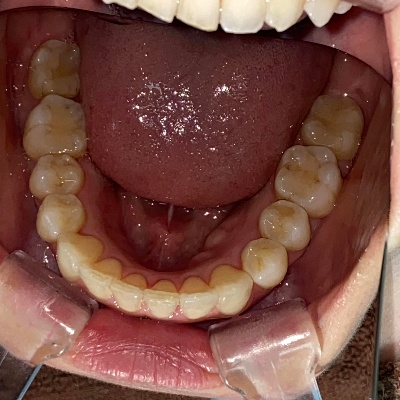

上下前歯の歯並びがガタガタしているのが気になる、きれいにしたいとのご希望で来院されました。

来院時の歯並び写真